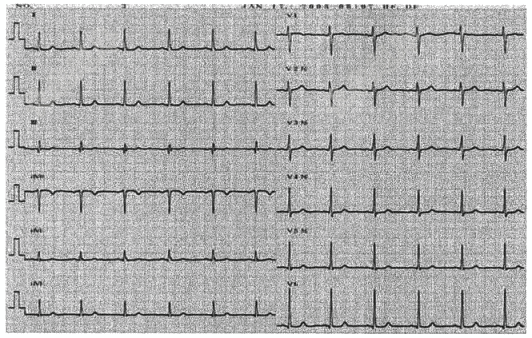

- 单项选择题男,71岁。既往高血压10年,心电图如图,诊断为( )

A、左心室肥厚

B、左束支传导阻滞

C、右心室肥厚

D、右束支传导阻滞

E、大致正常心电图